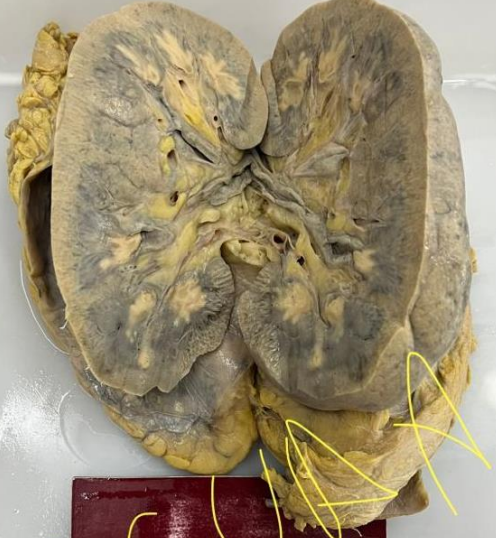

A

-Órgão: Rim.

-Descrição: Tamanho aumentado, estrutura anatômica alterada pela presença de inúmeras formações císticas de conteúdo líquido.

-Diagnóstico: Doença policística renal do adulto.